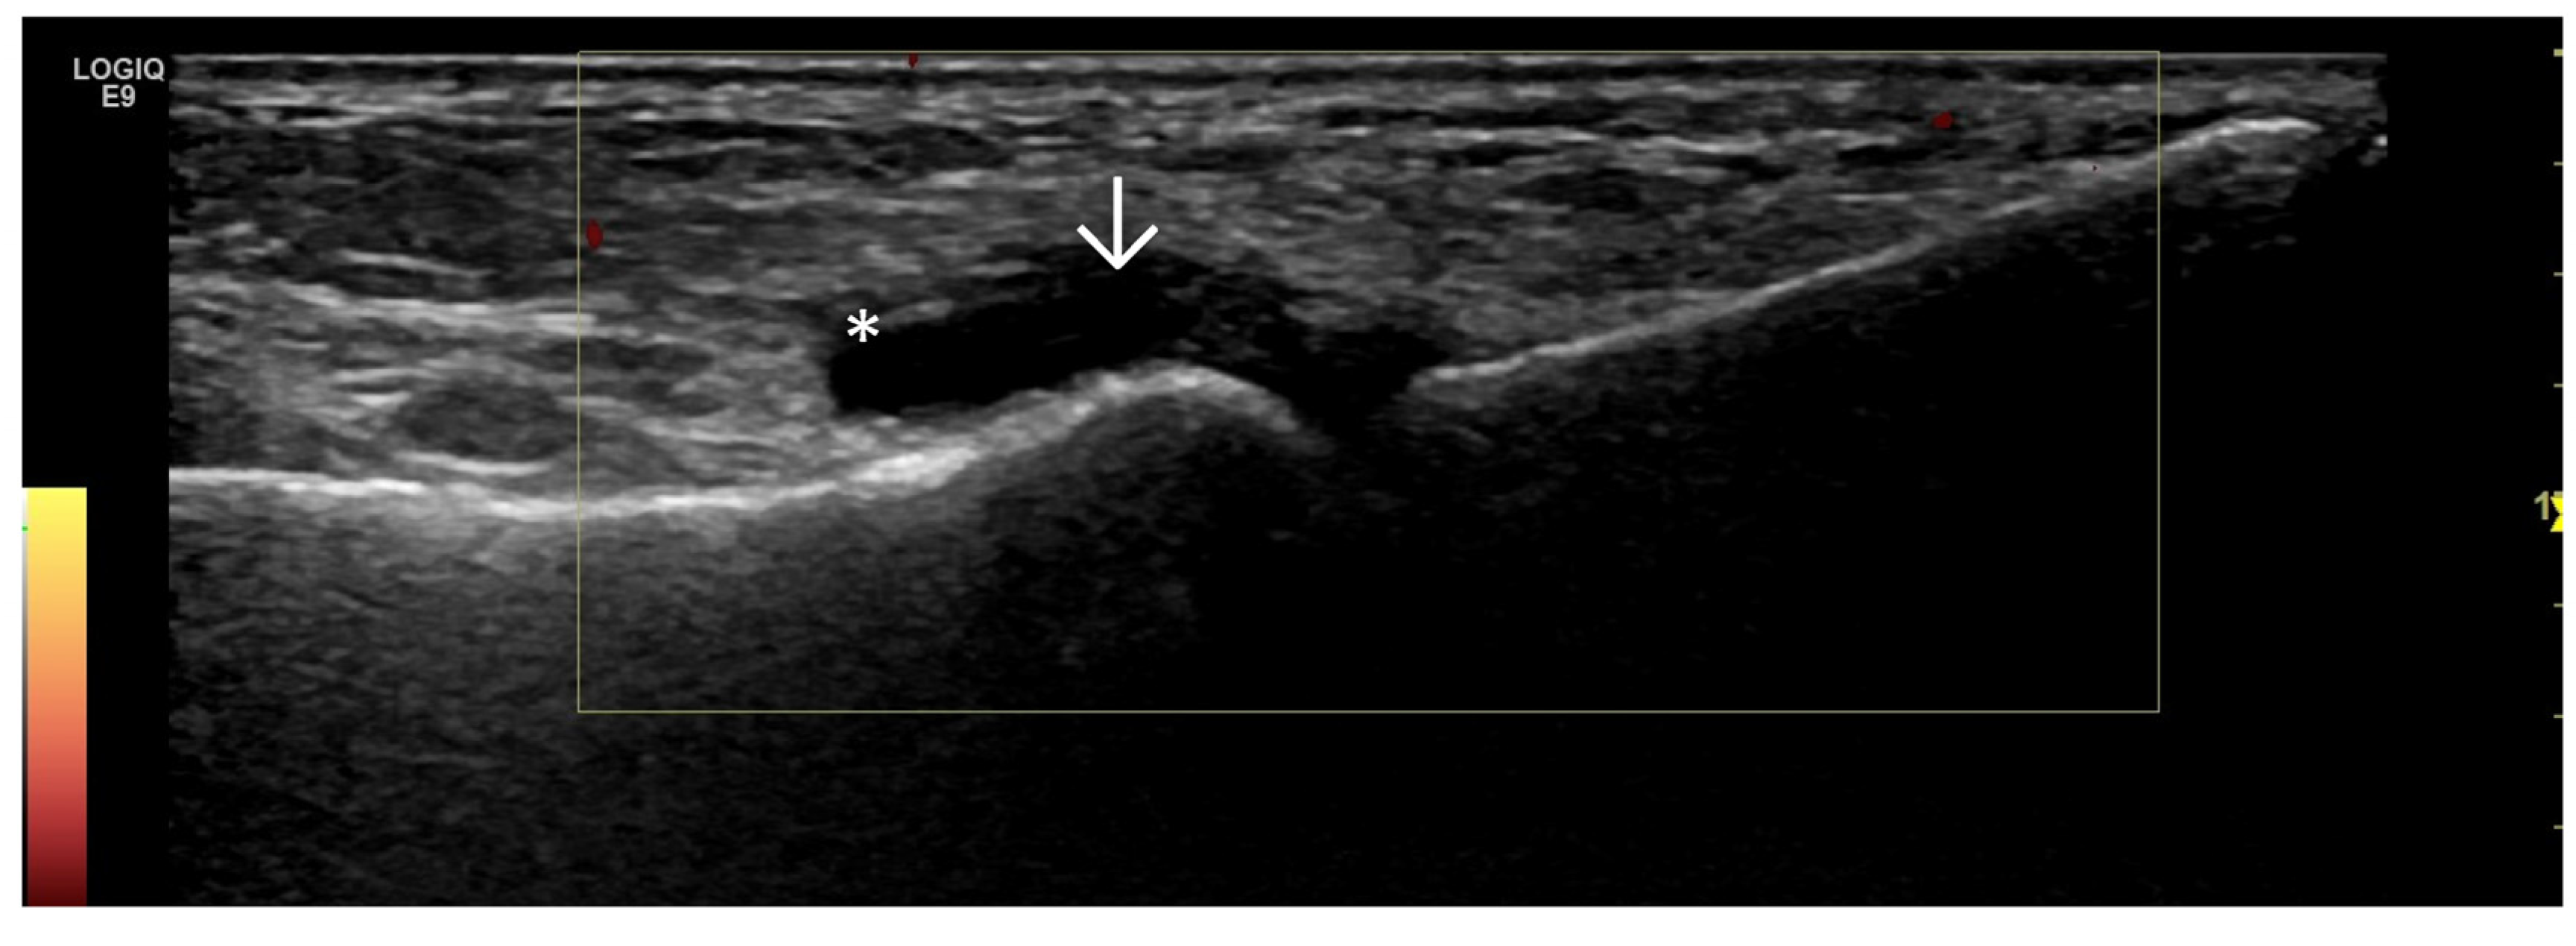

- Predominant synovial proliferation, fat pads, and Hoffa synovitis (with a small amount of intra-articular effusion);

4. Examples of US Phenotypes